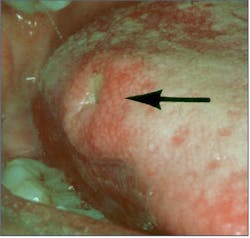

Median rhomboid glossitis (MRG) affects approximately 1% of adults. It has been described as an erythematous candidiasis unique to the midline central area on the dorsal tongue in front of the sulcus terminalis. This lesion has no papillae and is rhomboid in shape (figure 6).8

Usually asymptomatic, antifungal therapy will reduce clinical erythema and inflammation due to candida infection or completely resolve the lesion.9